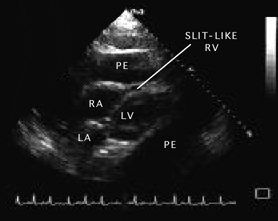

10. Tamponada cardiaca (pericardica) - cresterea cantitatii de lichid intrapericardic la volume foarte mari sau in mod brusc determina o crestere a presiunii exercitate asupra cordului producind:

o reducere dramatica a umplerii ventriculare in diastola (pana la colaps al cavitatilor drepte), cu scaderea consecutiva a debitului sistolic VD si VS;

Semne ecocardiografice:

lichid pericardic in cantitate mare (evidentiaza si dispunerea topografica a acestuia),

reducere a amplitudinii excursiei DE si pantei EF a valvei mitrale la prima diastola din inspir,

variatie inspir-expir > 40% a amplitudinii excursiei DE a valvei tricuspide,

colaps AD, VD (protodiastolic) si AS,

congestie 'fixa' a VCI (scadere < 50% in diametru proximal la inspir profund).

EcoCG in tamponada cardiaca